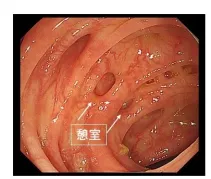

大腸憩室とは、腸管内圧の上昇により粘膜+粘膜筋板のみが腸管壁の抵抗減弱部位より脱出して発生する直径5mm程度のくぼみです(写真)。本邦では3/4が右側結腸に生じます。

大腸内視鏡検査を行うと10%くらいの頻度で見つかる比較的ありふれた病気です。憩室自体はあるだけでは無症状で、特に治療を必要としませんが、便秘などの誘因により炎症を起こしたり、出血を起こすと治療が必要となります。